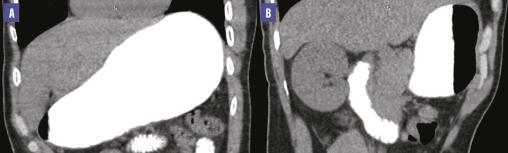

Une tomodensitométrie (TDM) abdominale met en évidence une compression de la troisième portion du duodénum par l’artère mésentérique supérieure associée à une importante dilatation de l’estomac et des deux premières portions du duodénum. L’angle aortomésentérique est mesuré à 12,2° et la distance aorte-artère mésentérique supérieure atteint 4,27 mm (fig. 1 et 2 ), ce qui a permis de poser le diagnostic du syndrome de la pince aortomésentérique.

Une tomodensitométrie (TDM) abdominale met en évidence une compression de la troisième portion du duodénum par l’artère mésentérique supérieure associée à une importante dilatation de l’estomac et des deux premières portions du duodénum. L’angle aortomésentérique est mesuré à 12,2° et la distance aorte-artère mésentérique supérieure atteint 4,27 mm (